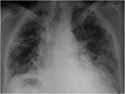

Resultados radiológicos

Los hallazgos radiológicos son los que se muestran a continuación.

Foto 1. Radiografía PA: Opacidades intersticiales de patrón reticular grueso, de predominio periférico, con áreas que sugieren patrón de “panal de abejas”.